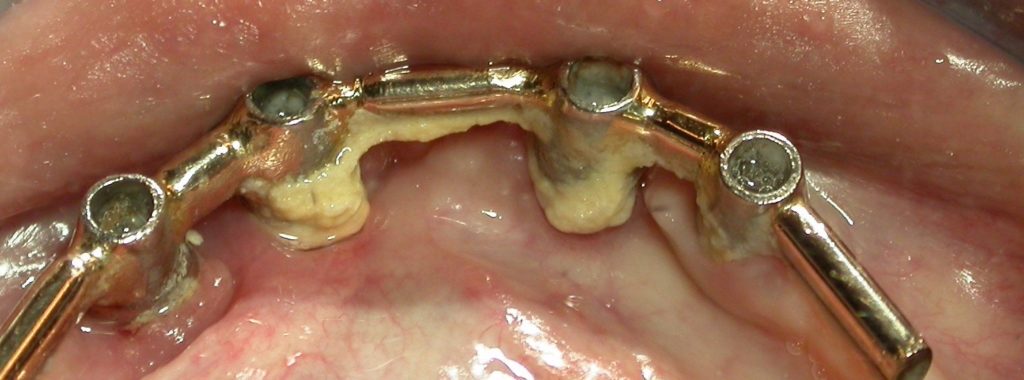

Le contrôle de plaque reste un élément primordial dès le placement d’implants, et lors de la réalisation de la prothèse, il faudra veiller à ce qu’il soit facilité. La connectique idéale est celle qui permettra la meilleure étanchéité pour éviter tout risque de contamination. Le risque de placer des prothèses scellées est la fuite potentielle de ciment.

Une séance de maintenance implantaire doit au moins comprendre une révision de l’anamnèse, un examen clinique et radiologique, un entretien motivationnel, un contrôle occlusal et l’élimination des dépôts durs et mous de toute la bouche. L’instrumentation ultrasonique permet un accès dans les poches autour des implants grâce à des inserts spécifiques en titane. Les aéropolisseurs assurent l’élimination des dépôts mous, certaines buses étant utilisées avec des poudres spécialement conçues pour la zone sous-gingivale.